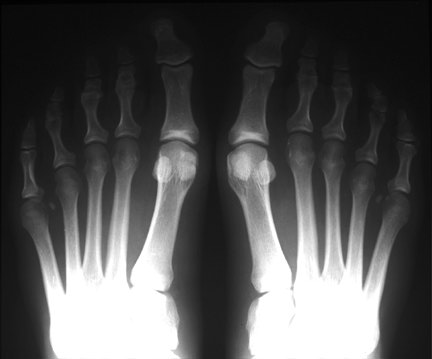

BilatHV:

This patient has a marked hallux valgus deformity in both feet. As the first toe migrates more and more to valgus, it presses against the second toe, and may aggravate dorsal clawing of the second toe, which is usually initiated by overload of the second metatarsal and synovitis of the metatarsophalangeal joint. Also note the relative hyperostosis of the second metatarsal shafts compared to the third and fourth, as well as dorsal rotation of the fibular sesamoids.

This patient has undergone bilateral osteotomy of the medial 1st metatarsal heads (“bunionectomy”). Unlike the Lapidus procedure, this procedure does not correct the underlying splaying of the 1st metatarsal, and can lead to instability of the first metatarsophalangeal joint. In this case, the hallux valgus has been overcorrected, and the patient now has a bilateral hallux varus. Bilateral osteotomies are noted in the 5th metatarsals for correction of “bunionette” deformities.